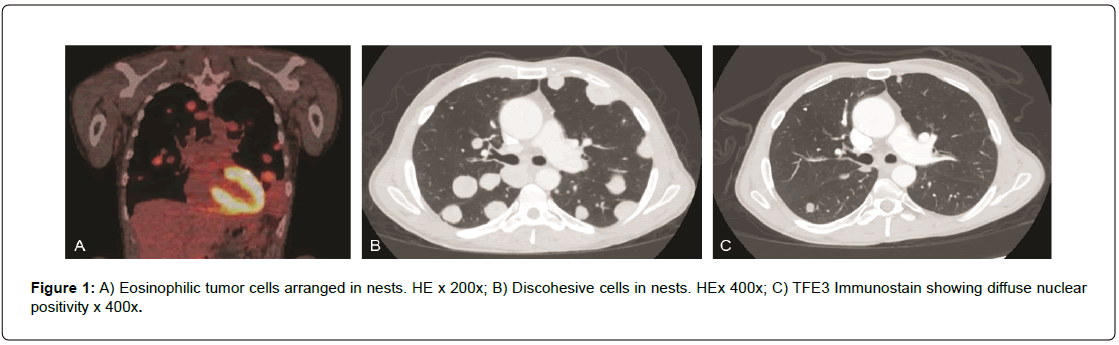

A 49-year-old white male presented for evaluation after a recent diagnosis of alveolar soft part sarcoma of the right buttock with extensive pulmonary nodular metastatic disease. A Positron Emission Tomography/Computed Tomography (PET/CT) scan done from skull base to mid-thigh showed multiple bilateral hypermetabolic pulmonary nodules with a right upper lobe nodule measuring 1.8 cm, a right upper lobe 2.2 cm lesion as well as pulmonary nodule in the left upper lobe measuring 2.8 cm, and a pulmonary nodule in the lingular segment measuring 3.8 cm with an SUV of up to 7. There was also a 4.9 cm × 3.2 cm soft tissue tumor mass in the right gluteus medius muscle with an SUV of 4.55 (Figure PET Axial Pelvis). Magnetic Resonance Imaging (MRI) of the brain noted numerous enhancing supratentorial anxd infratentorial nodules with surrounding vasogenic edema consistent with metastatic disease. The largest infratentorial lesion within the right cerebellar hemisphere measured 1.1 cm × 1.0 cm × 1.2 cm (Figure MR Brain). Diagnosis of alveolar soft part sarcoma was confirmed by biopsy of a left lung nodule as well as a CT guided needle biopsy of the right gluteal mass showed polygonal cells with eosinophilic granular cytoplasm, vesicular nucleus arranged in nest like pattern with a rich capillary vasculature (Figure 1a and Figure 1b). There was diffuse nuclear positivity for TFE3 supporting the diagnosis. (Figure 1c.)

Figure 1: A) Eosinophilic tumor cells arranged in nests. HE x 200x; B) Discohesive cells in nests. HEx 400x; C) TFE3 Immunostain showing diffuse nuclear positivity x 400x.